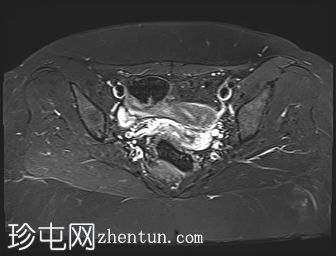

轴位

斜位T2加权像

子宫外底轮廓清晰,肌层较厚,将子宫内膜腔分隔成两个腔,纤维层较薄,向下延伸至宫颈外口。子宫内膜厚度正常,两个子宫腔交界区清晰,未见明显的实性局灶性病变。

卵巢卵泡形态正常,可见多个小卵泡,主要位于卵巢周边,无优势卵泡。未见实性或囊性肿块。

膀胱MRI表现正常。

未见盆腔软组织肿块或淋巴结肿大。

未见明显盆腔游离积液。

本病例展示了典型的纵隔子宫影像学表现:增厚的肌层隔膜将子宫内膜腔分隔成两个腔,并有一层薄的纤维隔膜延伸至子宫颈外口水平,符合完全纵隔子宫的特征。

纵隔子宫是最常见的先天性子宫畸形,可能导致流产率升高。

磁共振成像(MRI)是目前首选的影像学检查方法。

在MRI图像上,纵隔子宫通常大小正常,但每个子宫腔的形态均小于正常子宫腔。

隔膜可能由纤维组织(T2信号低)、肌层组织(中等信号)或两者共同构成,如本病例所示。